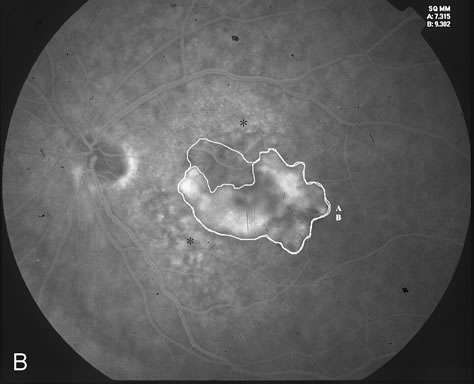

The classic and occult components of CNV are outlined in Figure 2. The percent of the CNV that is classic can then be determined as a proportion of the total CNV. In Figure 2A and B, the area of classic CNV measures 978 square microns and the total lesion measures 11,180 square microns. The classic component is thus 9% of the entire CNV and this lesion is classified as “minimally classic” CNV (defined as less than 50% classic CNV).23,40 The fluorescein angiogram demonstrates another mixed classic and occult CNV lesion in Figure 3. Using digital area measurements, the lesion in Figures 3A and B is composed of 79% classic CNV and fulfils the criteria for predominantly classic, subfoveal CNV that may benefit from verteporfin-PDT based on TAP findings.23,40 The TAP studies also demonstrated a visual benefit in eyes that had prior nonfoveal, thermal laser photocoagulation and subsequent recurrence of CNV below the fovea.23,40 In Figure 4A, subfoveal CNV recurrence in an eye with prior thermal photocoagulation is demonstrated. One month following verteporfin-PDT treatment, Figures 4B (early phase) and 4C (late phase) demonstrate characteristic hypofluorescence of the treated subfoveal CNV on fluorescein angiography.

Fig. 3. A. Fluorescein angiogram reveals predominantly classic CNV. B. Digital imaging outlines the classic component (A) and the entire lesion (classic and occult, marked as B). The area of classic component measures 7,315 square microns. The entire lesion measures 9,302 square microns. The areas marked with an asterisk correspond clinically to drusen. C. Greatest linear dimension (GLD) of the entire classic CNV measures 4,184 microns.

After qualifying for verteporfin-PDT based on clinical and fluorescein angiographic findings, informed consent is carefully obtained. Contraindications to PDT include porphyria, severe liver disease, pregnancy, or a known hypersensitivity to a photosensitizing agent. The greatest linear dimension (GLD) is determined with caliper measurement across the longest digital fluorescein angiographic diameter of leakage. The size of the area to be treated using the nonthermal 689 nm light should have a 500 μm border around the CNV, so a total of 1,000 μm should be added to the greatest diameter (or GLD) of CNV. The treatment area should extend no closer than 200 μm to the optic nerve, as recommended by the TAP studies.23,40 In Figure 3C, the area of CNV to be treated would be 4,184 plus 1,000 μm, or 5,184 microns.